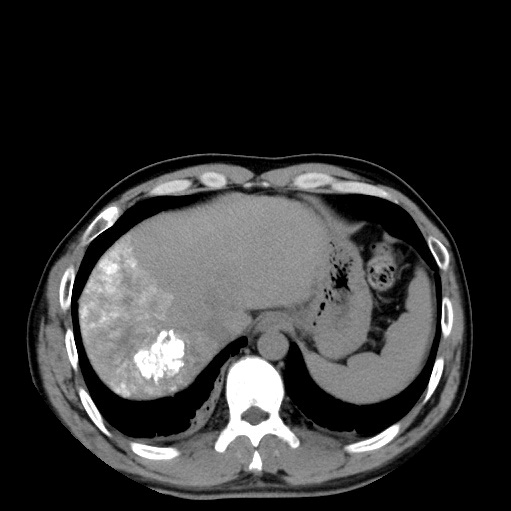

復(fù)查CT碘油填充肝癌病灶

按照治療計(jì)劃,行CT引導(dǎo)下微波消融術(shù),消融結(jié)束后肝癌病灶及其周邊部分肝組織被完全滅活。